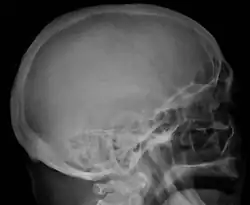

The diagnostic examination of a person with suspected multiple myeloma typically includes a skeletal survey. This is a series of X-rays of the skull, axial skeleton, and proximal long bones. Myeloma activity sometimes appears as "lytic lesions" (with local disappearance of normal bone due to resorption) or as "punched-out lesions" on the skull X-ray ("raindrop skull"). Lesions may also be sclerotic, which is seen as radiodense.[76] Overall, the radiodensity of myeloma is between −30 and 120 Hounsfield units (HU).[77] Magnetic resonance imaging is more sensitive than simple X-rays in the detection of lytic lesions. An MRI may supersede a skeletal survey, especially when vertebral disease is suspected. Occasionally, a CT scan is performed to measure the size of soft-tissue plasmacytomas. Nuclear Medicine Bone scans are typically not of any additional value in the workup of people with myeloma (no new bone formation; lytic lesions not well visualized on nuclear bone scan).

Skull X-ray showing multiple lucencies due to multiple myeloma -